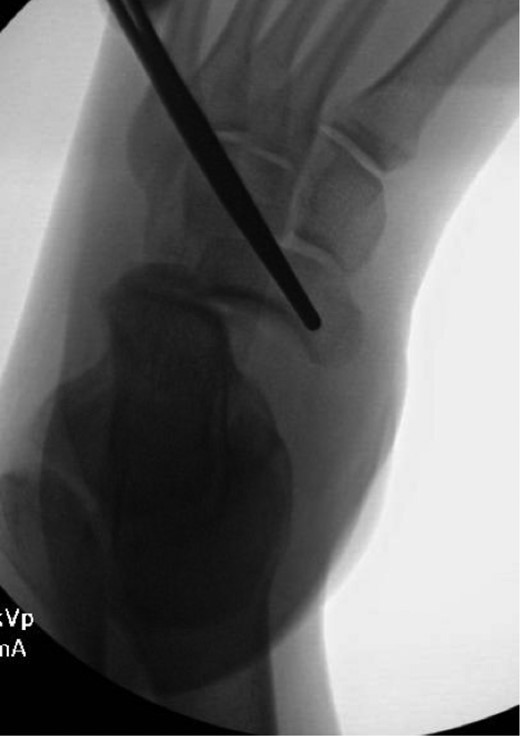

Once general anesthesia was induced, closed reduction was attempted using axial traction with the knee in flexion. Closed reduction was unsuccessful once again (Fig. 3) so the decision was made to attempt open reduction. An anteromedial approach was used dissect down to the talonavicular joint. Retractors were placed with care to avoid injury to tibialis anterior tendon or superficial peroneal nerve. The joint capsule was seen to be disrupted and further exposure revealed a thin, coronal fracture of the anteromedial aspect of the talar head measuring roughly 2 cm in length and 6 mm in thickness (Fig. 4). Once this fragment was removed, the subtalar and talonavicular joints were easily reduced. It was thought that this incarcerated fragment was the likely cause for the unsuccessful closed reduction. The talar head fragment was unamendable for stabilization due to its small size with poor healing potential, thus it was removed. The talonavicular joint was then percutaneously pinned in retrograde fashion with three K-wires (Fig. 5) to maintain anatomic reduction of the subtalar and talonavicular joints and the foot was splinted. At 2 weeks follow-up the patient was doing well and radiographs revealed no interval loss of reduction (Fig. 6).

Intraoperative AP view localizing the medial subtalar dislocation.